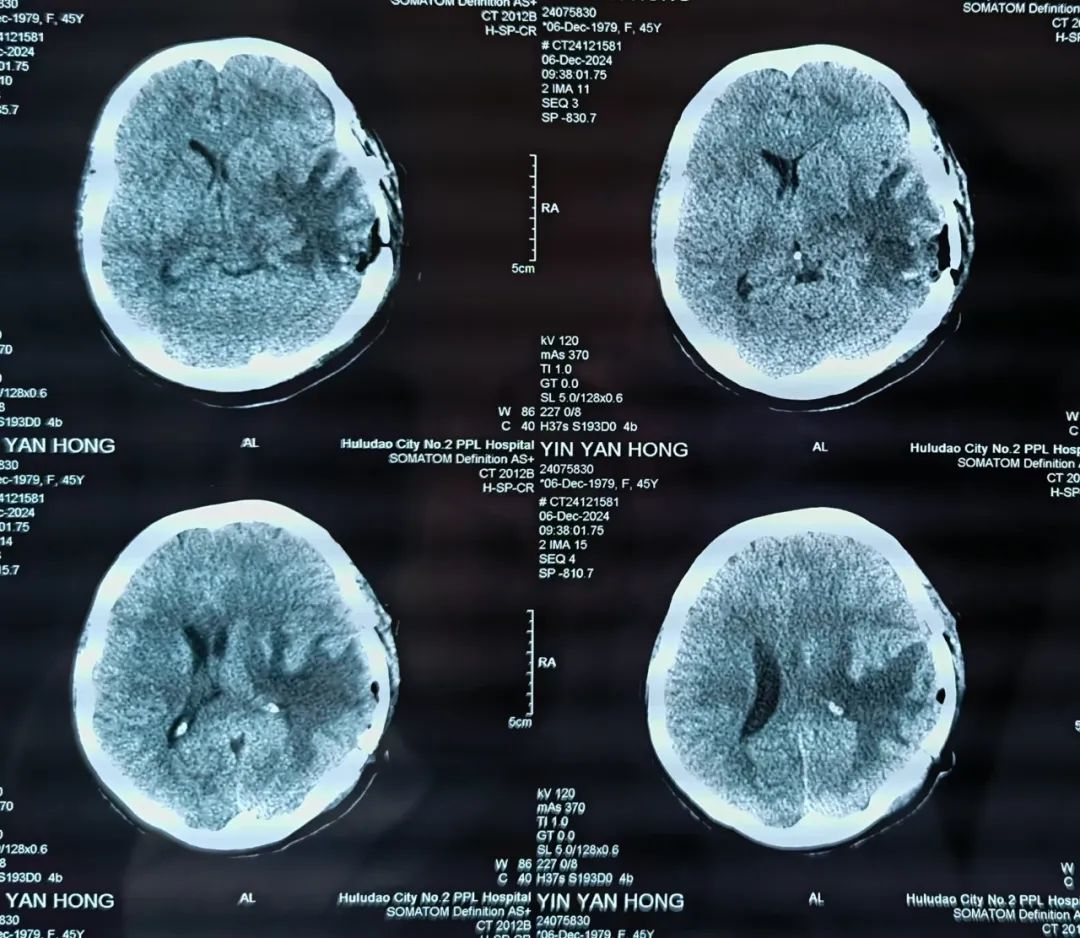

经过桑主任显微镜下精雕细琢,完整切除肿瘤,手术非常顺利。术后在神经外科护理团队的精心护理下,患者病情恢复良好,头痛、恶心、呕吐症状消失,言语流利,四肢活动良好,术后病理证实为脑转移瘤。手术不但为患者减轻了痛苦,提高了生活质量,也为后续的综合治疗赢得了时间。

患者术后CT影像